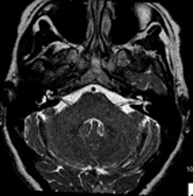

Prova diagnòstica no invasiva que consisteix en l'obtenció d'imatges d'alta definició anatòmica del cerbell mitjançant l'ús d'un camp electromagnètic i ones de ràdio (com un emissor i un receptor). No utilitza radiació ionitzant. Indicacions: problemes vasculars, pèrdua de memòria, epilèpsia, cefalea, malformacions, sospita de tumor, meningitis. - RM de Cais

- RM Cerebral (cranial)